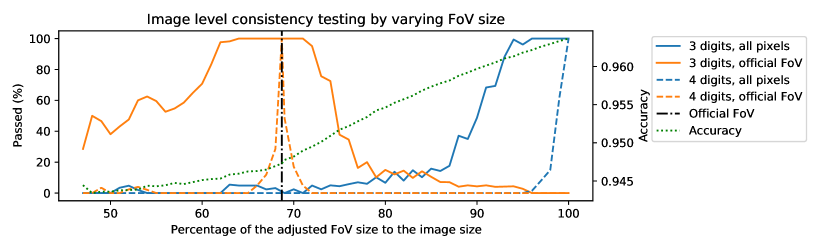

3.3.2 Sensitivity of the image level consistency test

To quantitatively characterize the sensitivity of the test to changes in the region of evaluation, we carried out a simulation treating annotation #1 as ground truth and annotation #2 as segmentation for all 20 images in the DRIVE test set. The FoV masks were gradually dilated to cover the images; for each mask size, the performance scores were calculated and rounded to 3 and 4 digits; and the tests derived in subsection 3.3.1 were applied to the scores to check whether they were computed under the original FoV masks or using all pixels of the images. The percentages of image level scores passing the tests at certain mask sizes are plotted in Figure 2 along with the average accuracy to illustrate the bias caused by the adjustment of evaluation region. The first thing to observe is that varying the size of the evaluation region has a remarkable effect on the accuracy scores. However, when the performance scores are rounded to 4 digits, a deviation as little as 1% from the assumed region makes the test fail on more than 50% of the 20 test images, as can be seen by the steep drop in the corresponding dashed lines around the size of the official FoVs (69% of the image size) and at 100% of the image size. The increased uncertainty of rounding to 3 digits widens the acceptance window (solid lines) and about 50% of the scores pass despite a 15% change in the size of the evaluation region. However, the passing rate drops to about 5% at the opposite assumptions, indicating that the two edge cases can still be distinguished by the test. The analysis suggests that the consistency test is able to distinguish the cases where the official (or slightly differing) FoV masks were used from those cases when all (or almost all) pixels of the images were included in the evaluation.

Similarly to the image level analysis, the aggregated figures must pass the test if the assumptions are met. However, due to the increased numerical uncertainty, it is questionable whether the sensitivity of the test is high enough to distinguish the two corner cases we are concerned with. As before, a quantitative characterization of sensitivity can be obtained by varying the size of the evaluation region, but this time checking whether the aggregated figures pass the test with the , , numbers extracted according to the hypotheses. According to the results shown in Figure 4, a 15% deviation in size from the hypothesised region causes the test to fail when the scores are reported to 4 digits. With rounding to 3 digits, the two corner cases are still distinguished by the test. However, if the region of evaluation is between 77%-87% of the image size, the scores can pass the test with either assumption.